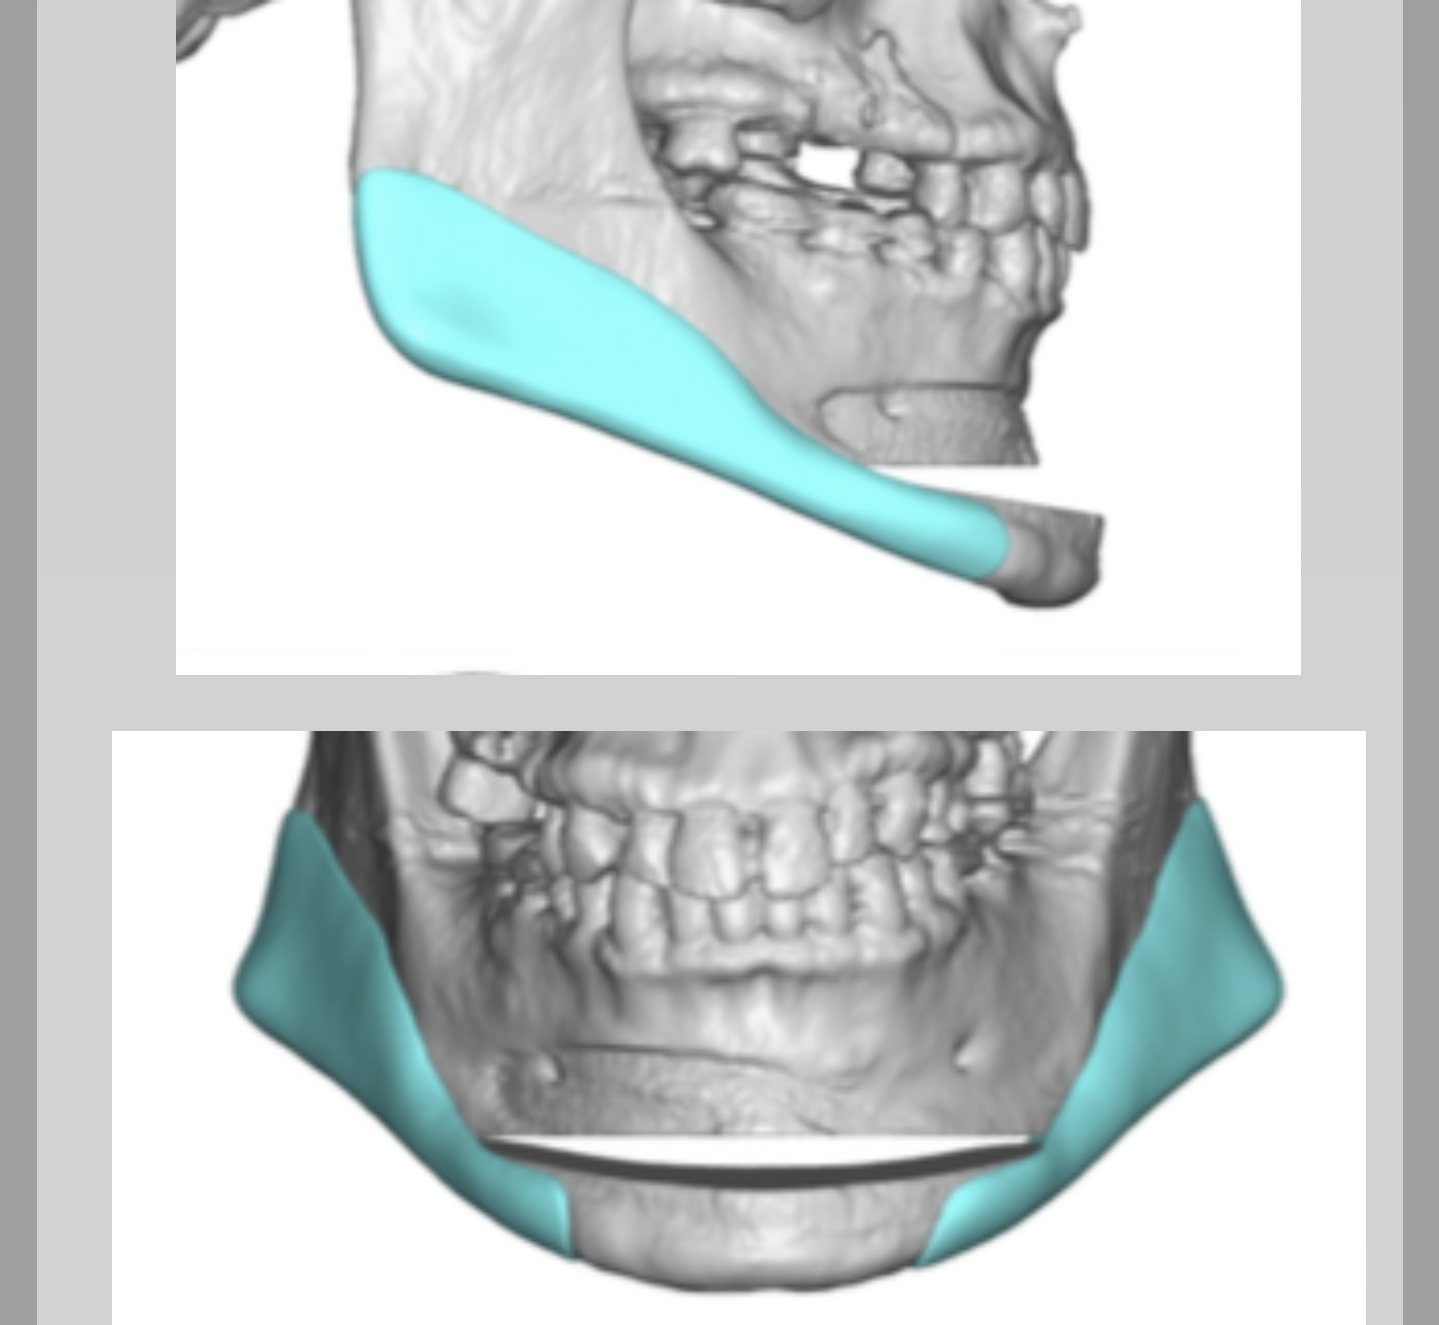

based off his bottom lip Im guessing his mentolabial fold is kinda deepChin shouldn't just be extended vertically like that it depends on other factors - his MPA also affects this so recommending him to do a vertical genioplasty can cause a bad step off regardless of bone grafts and cause aesthetic issues like ballsack chin

View attachment 4832969

Eppley is smart as fuck as he knows about this so he combines it with implants to keep the mandibular border continuous but now you are just making it way more expensive and complicated

You also have to assess this with respect to the mentolabial fold which we can't guess from this front profile

Also any type of genioplasty focussing on advancement and height will make his chin narrower due to the viewing angle

a T-split mini ching wing solves any of these problems of a regualr genioplasty.Chin shouldn't just be extended vertically like that it depends on other factors - his MPA also affects this so recommending him to do a vertical genioplasty can cause a bad step off regardless of bone grafts and cause aesthetic issues like ballsack chin

a T-split mini ching wing solves any of these problems of a regualr genioplasty.

Firstly this is some bullshit done by Safi of all people lol go read how shit of a surgeon he is on r/jawsurgery

just to get the idea across, i wouldn't recoomend this kind of design

I mentioned that i dont like the execution from dr. Safi in this case.Firstly this is some bullshit done by Safi of all people lol go read how shit of a surgeon he is on r/jawsurgery

Secondly explain how this fixes any of the issues I talked about

View attachment 4843627

Nothing here indicates it can avoid Pharaoh's chin or reduce the step off

If you look at the diagram provided you can literally only go Anteriorly or Posteriorly rotation would cause a crazy step off - even worse than a genioplasty step off